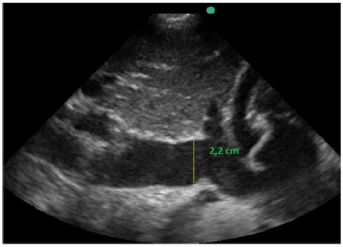

Também foi feita a mensuração da cava na janela subcostal 4 câmaras caval. O seu valor é maior de 2,2 cm e tem variabiliadade menor que 50% aos movimentos respiratórios ainda em ventilação espontânea, conforme a imagem apresentada.

Com base nessas informações e nas imagens, a estimativa da pressão sistólica da artéria pulmonar é de